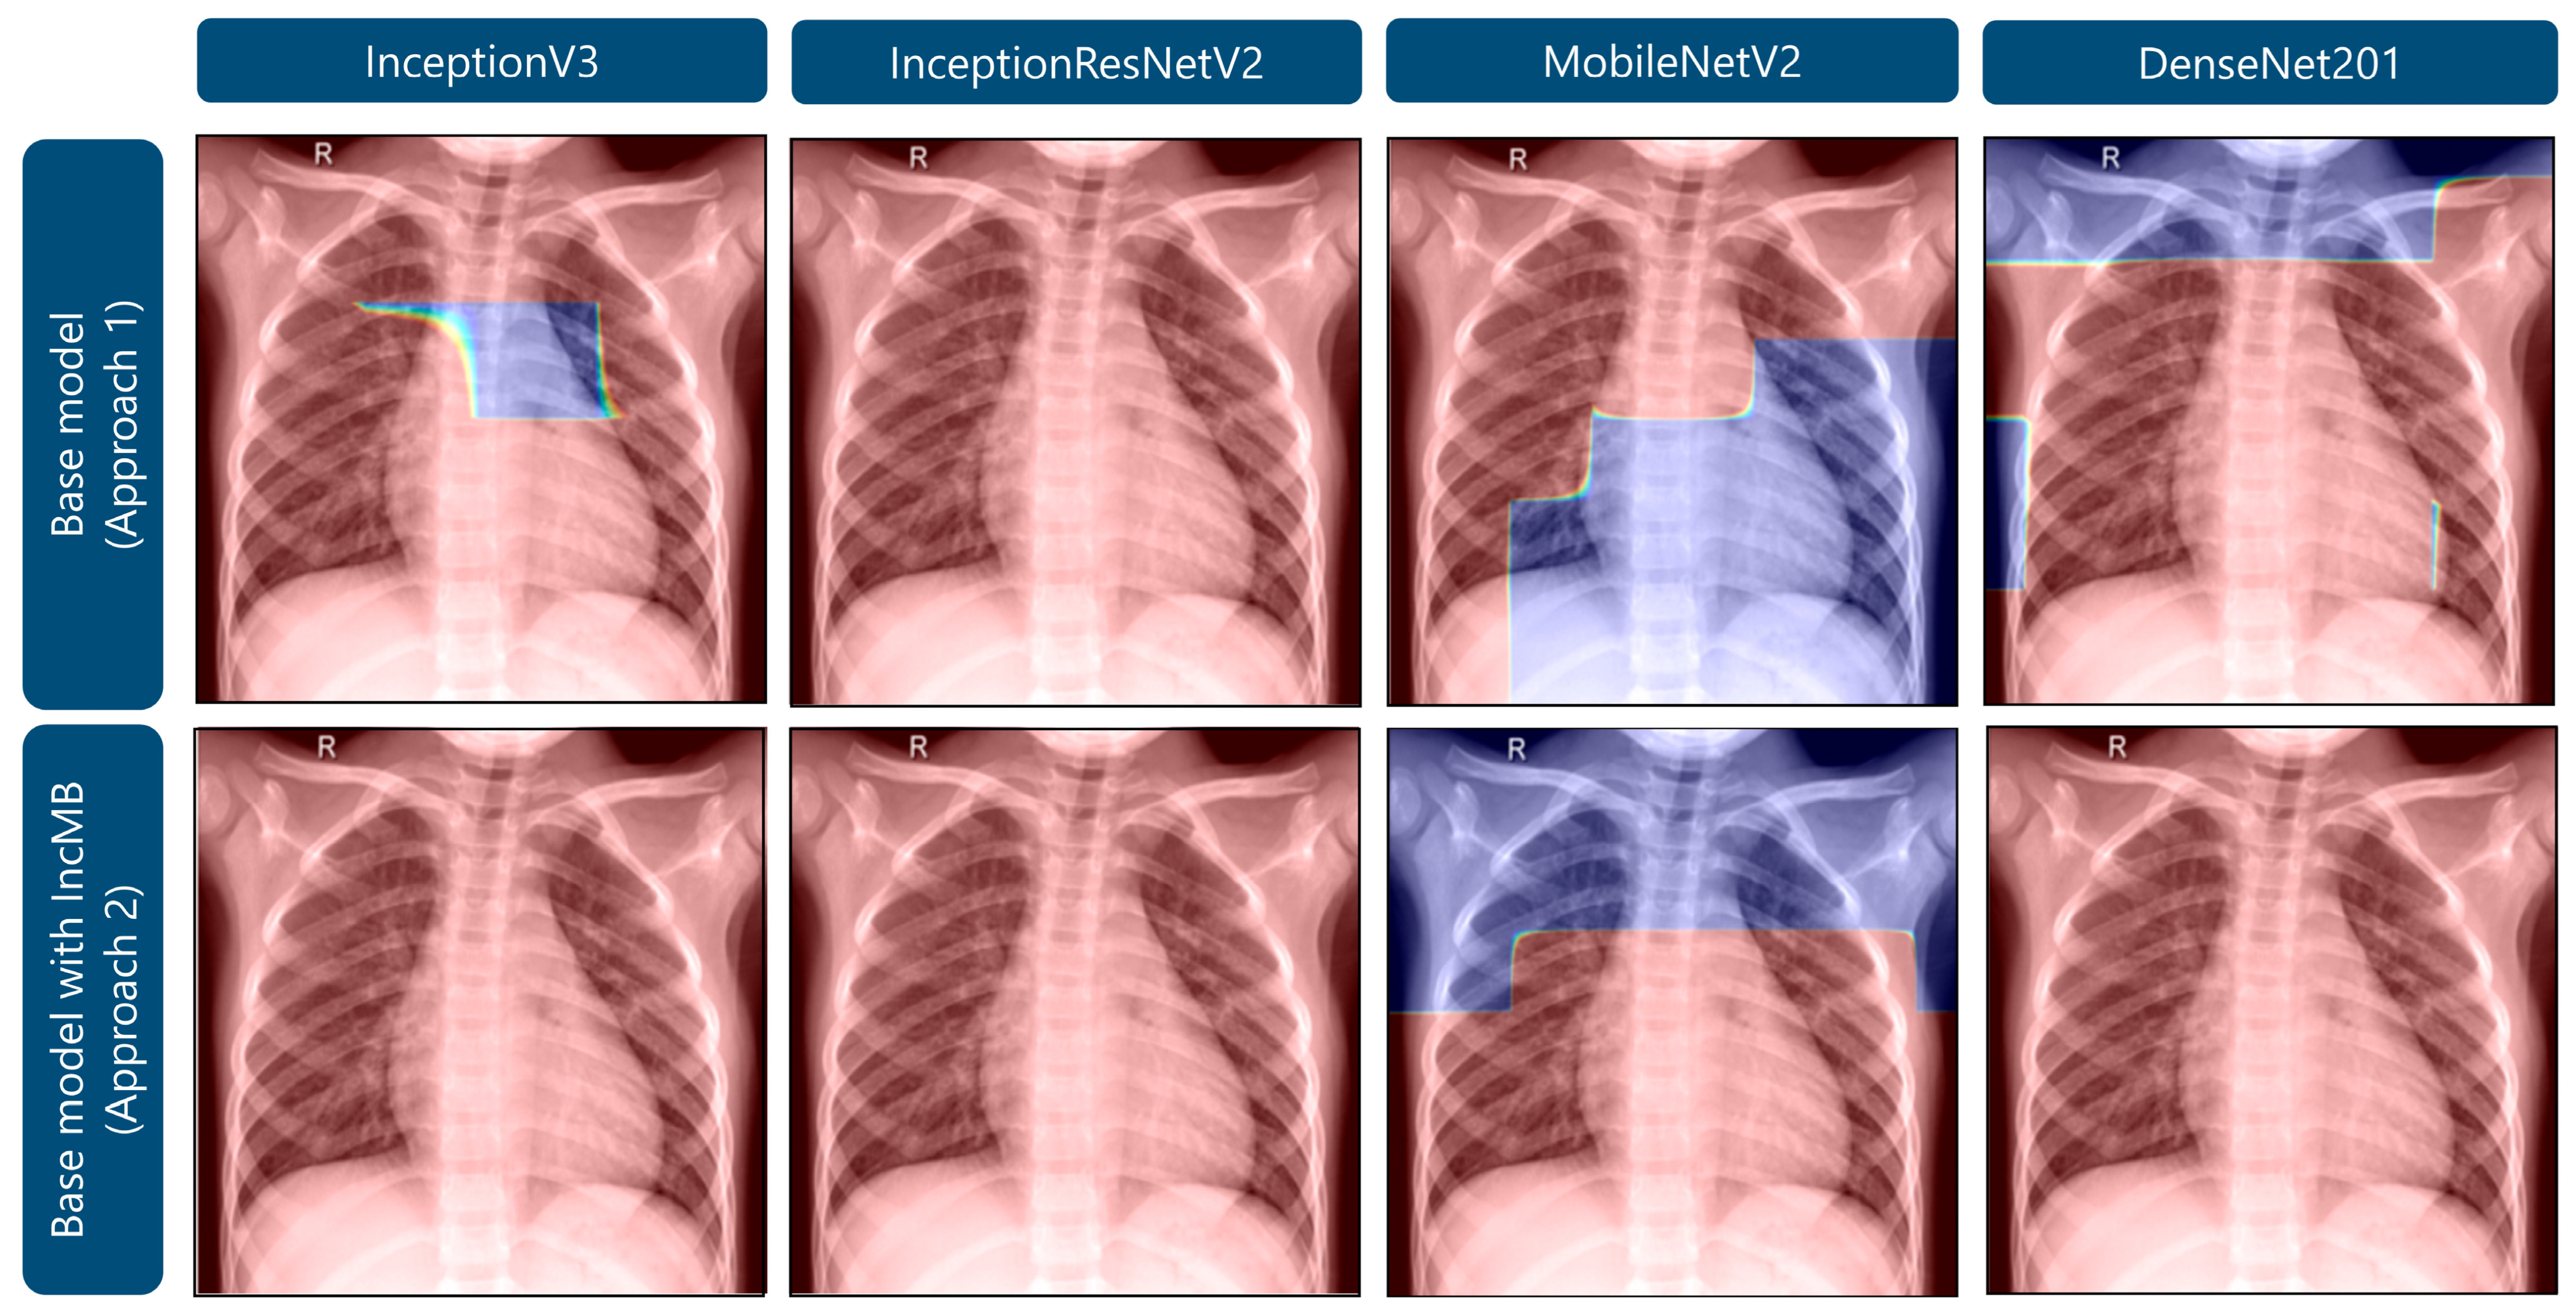

| Transfer Deep Learning Model | Classification Approach | Accuracy | F1-Score | Precision | Recall | Specificity |

|---|---|---|---|---|---|---|

| InceptionV3 | Base model | 0.9633 | 0.9529 | 0.9592 | 0.9471 | 0.9117 |

| Base model with IncMB | 0.9710 | 0.9630 | 0.9659 | 0.9603 | 0.9369 | |

| InceptionResNetV2 | Base model | 0.9676 | 0.9595 | 0.9536 | 0.9659 | 0.9621 |

| Base model with IncMB | 0.9812 | 0.9761 | 0.9781 | 0.9742 | 0.9590 | |

| MobileNetV2 | Base model | 0.9113 | 0.8961 | 0.8763 | 0.9322 | 0.9779 |

| Base model with IncMB | 0.9582 | 0.9451 | 0.9640 | 0.9297 | 0.8675 | |

| DenseNet201 | Base model | 0.9676 | 0.9579 | 0.9704 | 0.9470 | 0.9022 |

| Base model with IncMB | 0.9727 | 0.9656 | 0.9629 | 0.9684 | 0.9590 |